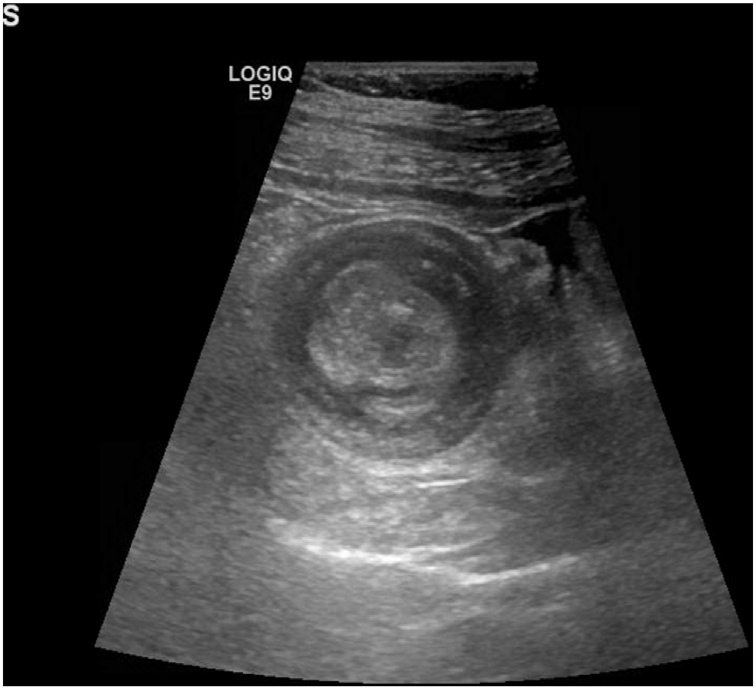

Doughnut Sign on ultrasound in a patient with Intussusception

Doughnut Sign

Intessusception

Intussusception